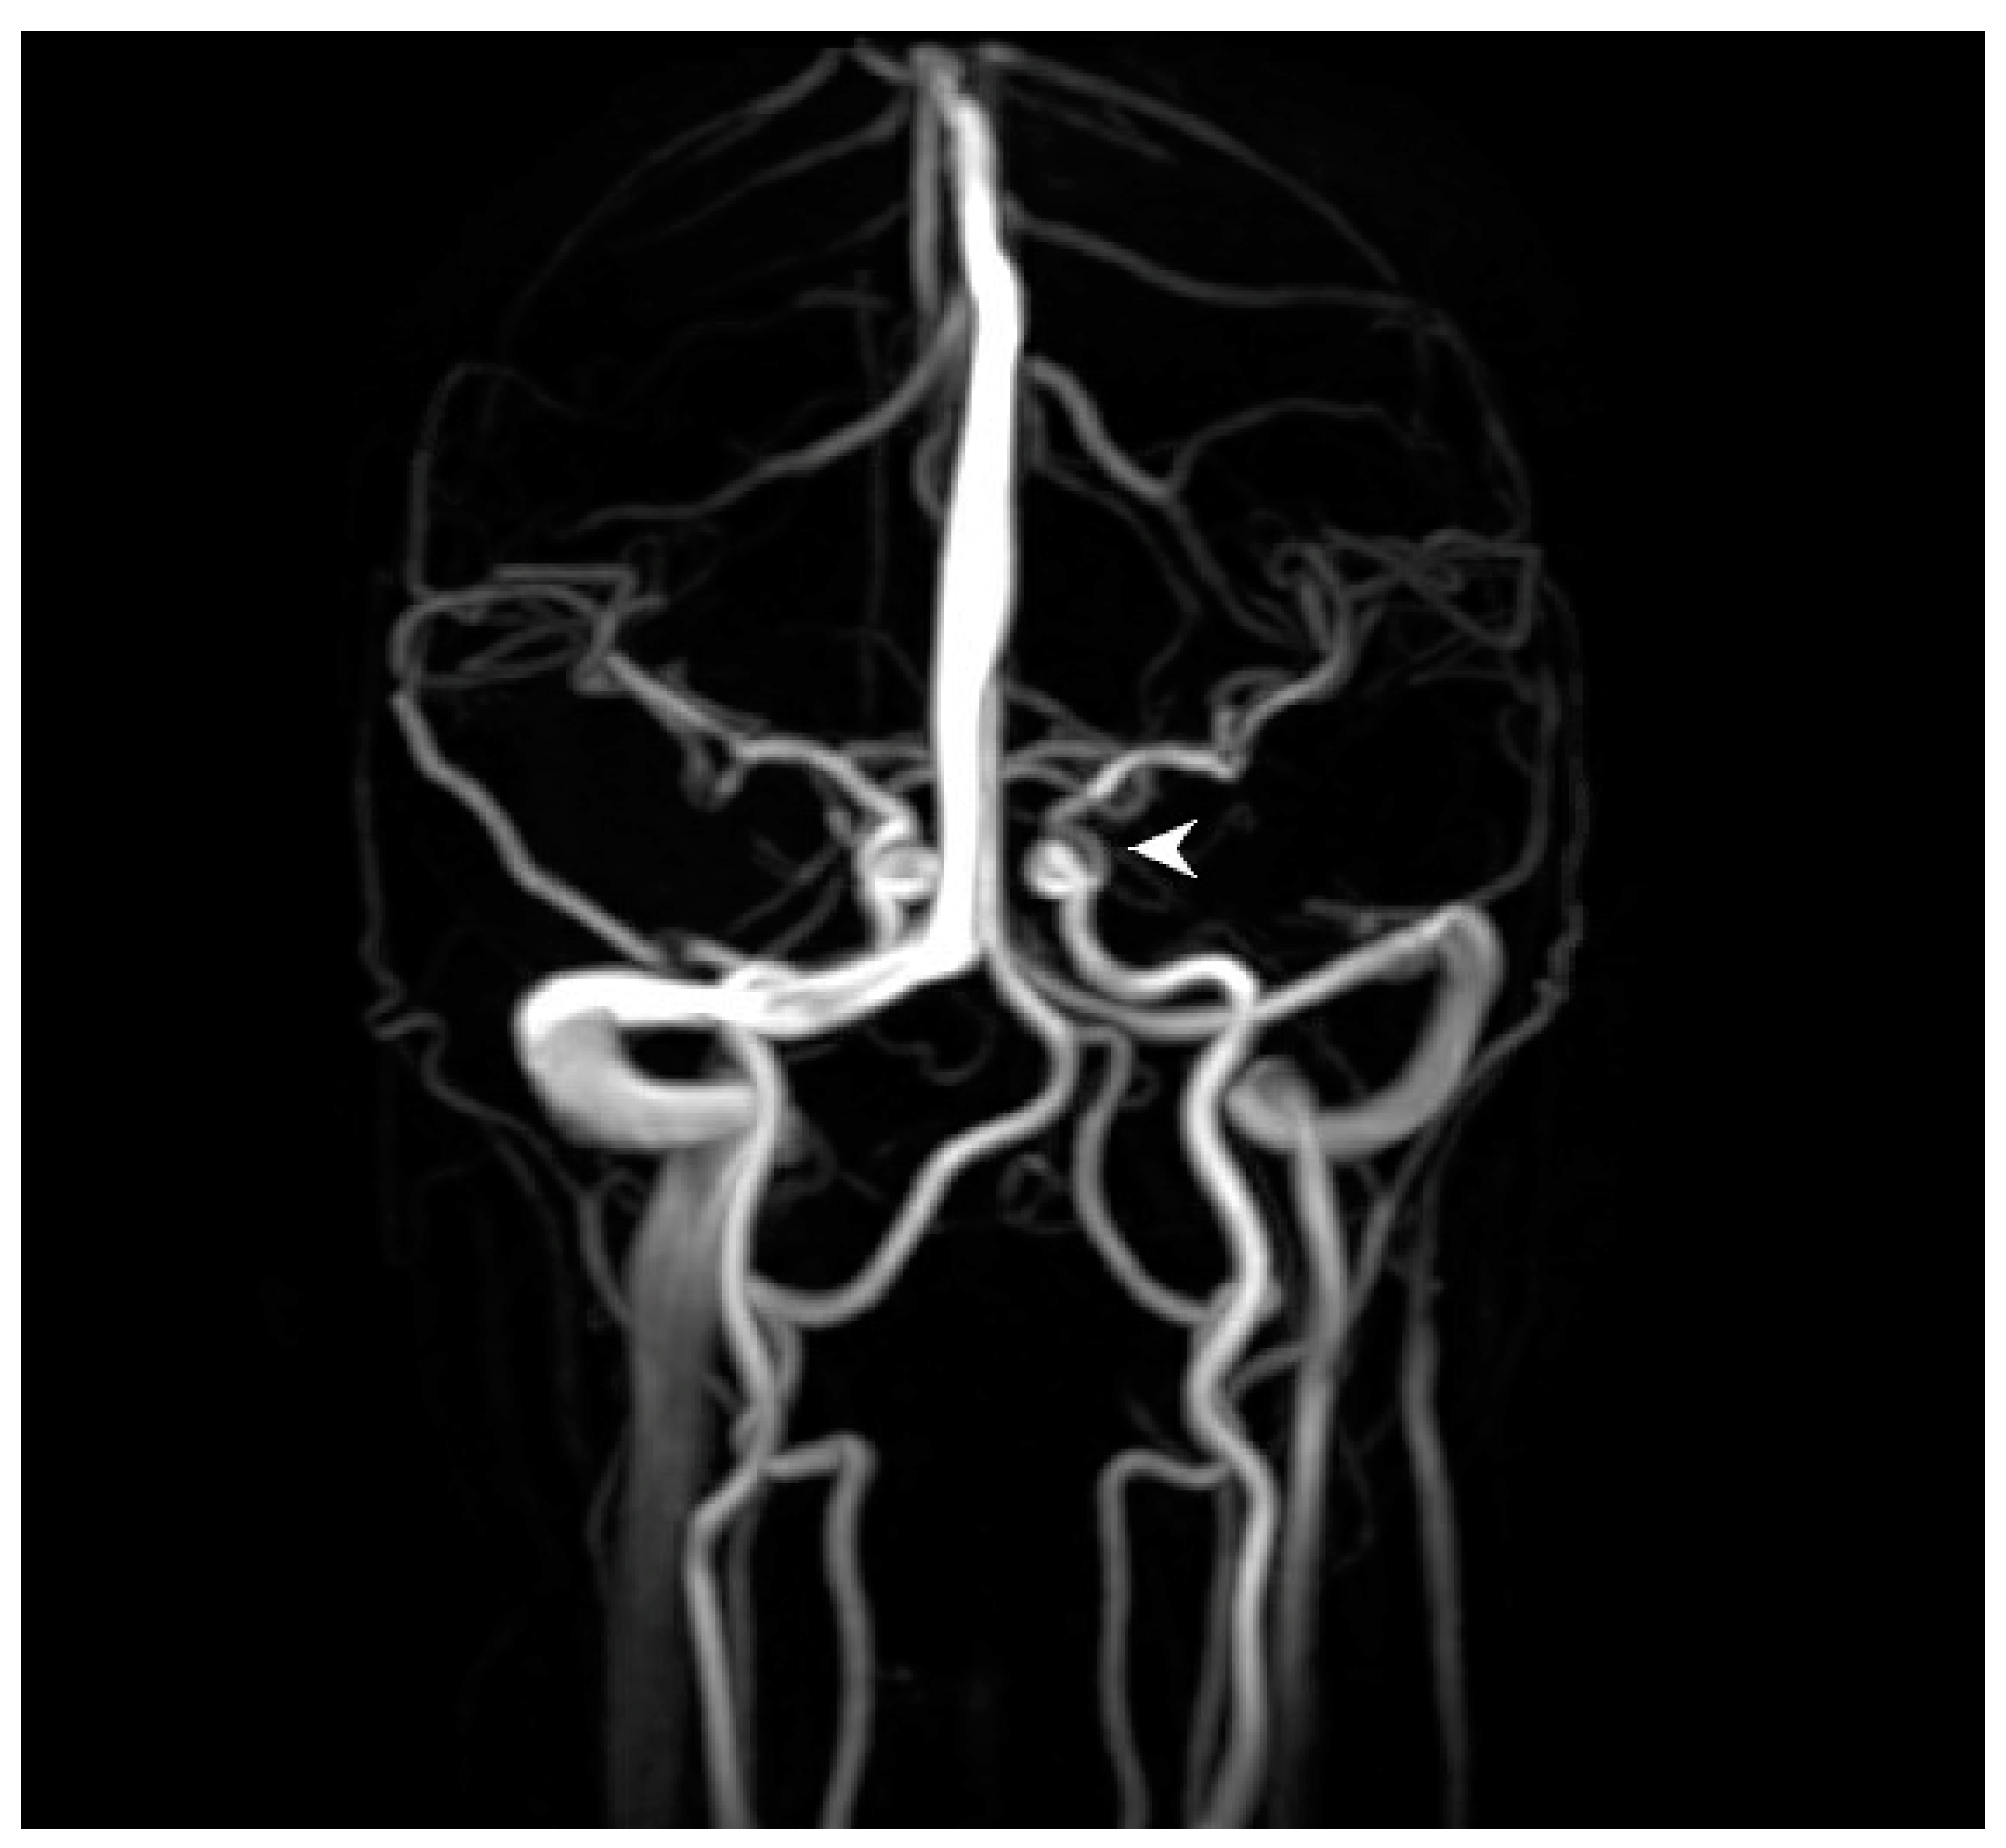

A 28-year-old woman with a history of migraines, prior tobacco use, narcolepsy, basilar artery occlusion (thought to be secondary to chiropractic manipulation) with resulting internuclear ophthalmoplegia without persistent defects, and asymptomatic left internal carotid artery (ICA) paraophthalmic aneurysm underwent a flow diversion procedure for the ICA aneurysm. She reported “I can’t see out of the top of my left eye” upon awakening in the postoperative care area. Emergency magnetic resonance imaging (MRI) showed no evidence of acute infarct, hemorrhage, or other intracranial abnormality. Magnetic resonance angiography/venography (MRA/MRV) revealed postprocedural changes of the left ICA but no other abnormalities of the intracranial vasculature (Figure 1).

Figure 1. Brain magnetic resonance angiography (MRA) immediately prior to ophthalmic examination shows anticipated changes from the recent revascularization procedure with persistent filling of the 2 mm supraclinoid segment aneurysm (arrowhead), without other abnormalities of the major intracranial vasculature.